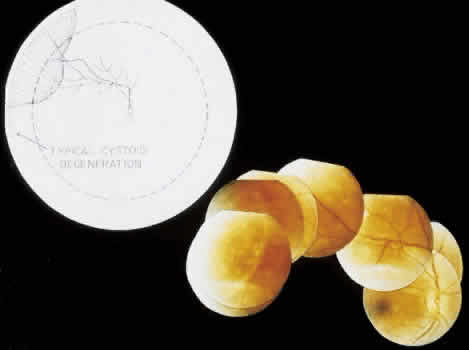

retinal layer; it rarely requires treatment.  Fig. 19. Clinical appearance of typical degenerative retinoschisis: diagram of involved

area and ocular fundus photographs showing optic disc, macula, and

posterior portion of schisis. Within the schisis and adjacent to

the margin is coarse stippling related to broken retinal pillars. Fig. 19. Clinical appearance of typical degenerative retinoschisis: diagram of involved

area and ocular fundus photographs showing optic disc, macula, and

posterior portion of schisis. Within the schisis and adjacent to

the margin is coarse stippling related to broken retinal pillars.